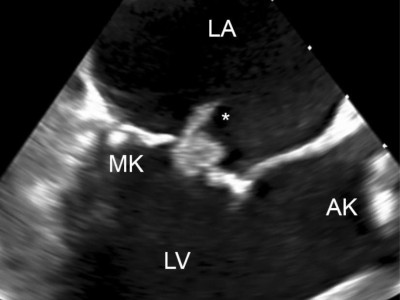

Endokarditisprophylaxe vor Zahnextraktion?

Ein 76-jähriger Patient, der vor zwei Jahren einen transfemoralen Aortenklappenersatz (TAVI) erhalten hat, stellt sich vor geplanter Zahnextraktion in der hausärztlichen Praxis vor. Ist hier eine Endokarditisprophylaxe angezeigt und wenn ja, wie sollte sie erfolgen?

DGIM Podcast-Reihe - Frailty/© (M) David L / peopleimages.com / Stock.adobe.com (Symbolbild mit Fotomodell), Junge Frau misst Blutdruck bei älterer Frau/© CasarsaGuru / Getty Images / iStock (Symbolbild mit Fotomodellen), Ältere Dame nimmt Tabletten ein/© Satjawat / stock.adobe.com (Symbolbild mit Fotomodell), Älterer Mann schaut kritisch auf Tabletten/© Mediteraneo / stock.adobe.com (Symbolbild mit Fotomodell), Blutabnahme/© Grafvision / stock.adobe.com (Symbolbild mit Fotomodellen), Frau auf einem Laufband mit Elektroden am Oberkörper/© technotr / Getty Images / iStock (Symbolbild mit Fotomodell), Ältere Dame in Reha/© W PRODUCTION / stock.adobe.com (Symbolbild mit Fotomodellen), Arzt berät Patienten zu Pillen/© crizzystudio / stock.adobe.com (Symbolbild mit Fotomodell), Frau misst Blutdruck/© Microgen / stock.adobe.com (Symbolbild mit Fotomodell), Blutabnahme bei einem Jungen/© Kalim / Stock.adobe.com (Symbolbild mit Fotomodellen), CT-Koronarangiographie eines Patienten mit Plaque im RIVA/© Springer Medizin, Junge Patientin im Gespräch mit einer Ärztin/© FatCamera / Getty Images / iStock (Symbolbild mit Fotomodellen), Alte Frau hält Sportbälle in Fitnessstudio hoch/© Robert Kneschke / stock.adobe.com (Symbolbild mit Fotomodell), Lipidprofil/© gamjai / stock.adobe.com, Koronarangiografie der Herzkranzarterien/© S. Dörr, Bild einer Endokarditis der Mitralklappe/© C. Stremmel, Search Icon, Person hält Tablette und Glas/© bilderstoeckchen / stock.adobe.com (Symbolbild mit Fotomodell), Ultraschall bei einem älteren Patienten/© Alex Potemkin / Getty Images / iStock (Symbolbild mit Fotomodellen), EKG befunden mit System - EKG Essential/© Springer Medizin Verlag GmbH